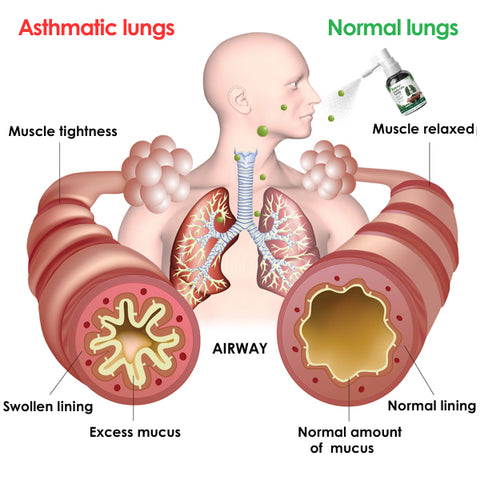

Crafted with precision from natural plant extracts, this innovative spray delivers soothing relief and improved lung function by effectively clearing mucus and waste, thus promoting optimal respiratory well-being.

Respira™ Lung Care Spray employs an advanced delivery mechanism, emitting a fine mist directly into the airways for optimal results. Upon application, the gentle mist coats the respiratory system precisely, ensuring targeted action. This approach maximizes the spray’s efficacy, fostering lung health and thorough respiratory cleansing.